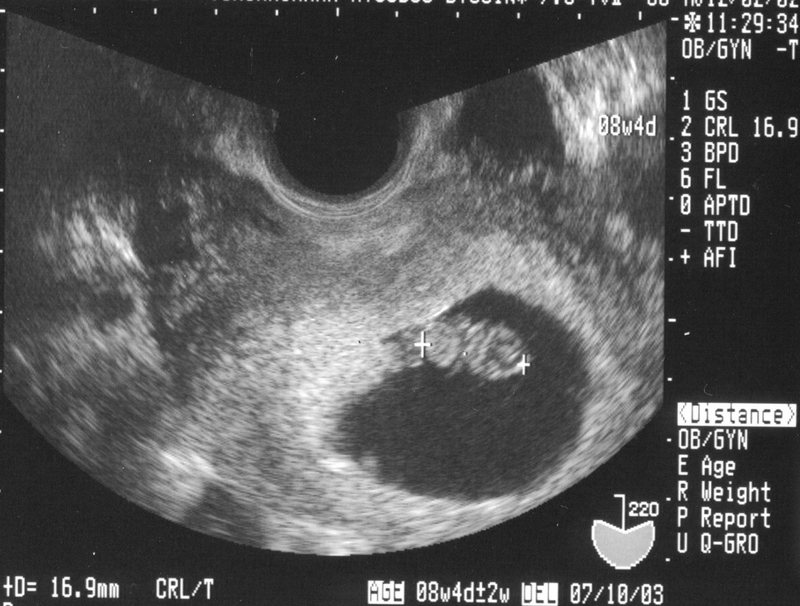

Siêu âm từ tuần thứ 5 - 8 của thai kỳ

Đây là lần siêu âm thai cơ bản và rất cần thiết. Siêu âm ở thời điểm này khẳng định được chính xác xem mình có đang mang thai hay không và xem phôi thai đã làm tổ đúng vị trí trong buồng tử cung hay chưa.

Ở tuần thai này chúng ta cũng có thể xác định và nghe được tim thai. Khi siêu âm các mẹ sẽ có một trải nghiệm vô cùng hạnh phúc với niềm vui vô bờ xen lẫn hồi hộp khi lần đầu được nghe nhịp tim của bé.

Siêu âm cân nặng thai nhi có chính xác không? 3 Siêu âm từ tuần thứ 5 - 8 của thai kỳ là mốc cơ bản và rất cần thiết